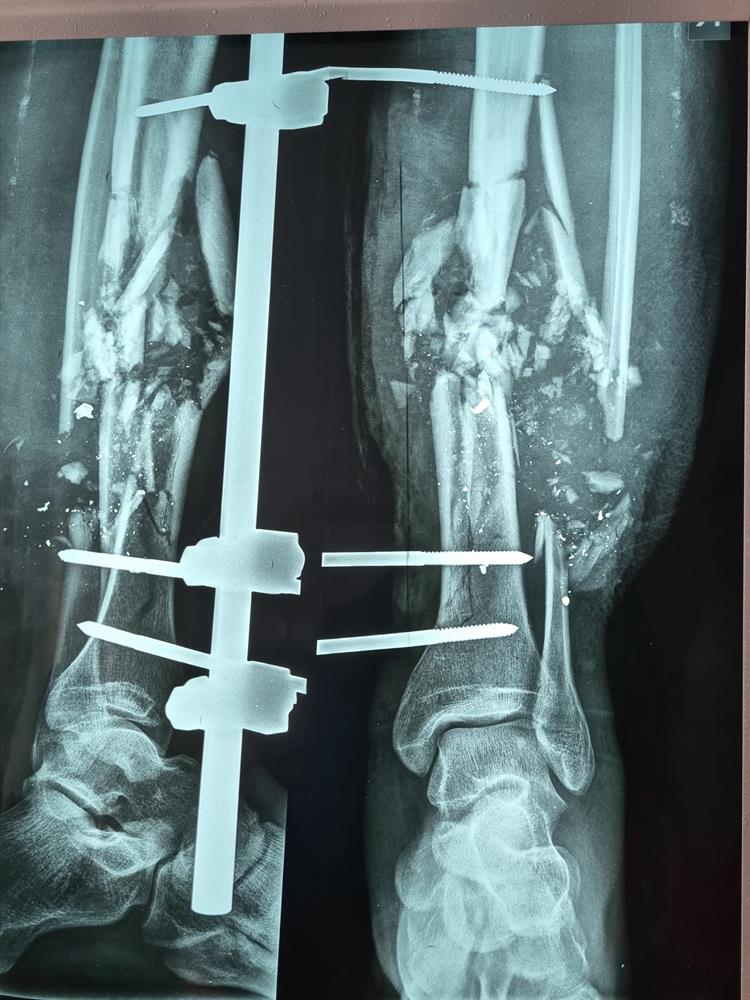

Samozřejmostí úspěšné a bezpečné mise je kvalitní vybavení sanitky a zkušenosti lékařů. Posádka se totiž musí umět vypořádat se velmi širokým spektrem zranění a nemocí. „Naše práce zahrnuje třeba péči o onkologicky nemocné, kteří nadále nemohou být léčeni ve svých zařízeních. Nejen že jsou ta zařízení třeba ostřelována, ale na Ukrajině došlo k centrálnímu zhroucení distribuce léků. To je pro vážně a chronicky nemocné zásadní problém. Musíme je proto dopravit někam, kde dostanou pomoc, kterou potřebují. Druhou skupinou pacientů jsou přímo zranění z války, kdy vozíme především děti se zlomenými končetinami, postřelené, se šrapnely v těle. Tam je ta péče mnohem náročnější a nevyzpytatelnější a opravdu je potřeba kvalitně vybavený vůz, není možné tyto zraněné převážet jen tak nějakým náklaďákem. Už jen ten fakt, že zranění musí podstupovat několik hodin jízdy v evakuačních vlacích bez jakýchkoliv tišících prostředků je opravdu katastrofa,“ říká s třesoucím se hlasem Prchal, když vzpomíná na pacienty, které během misí poznal.